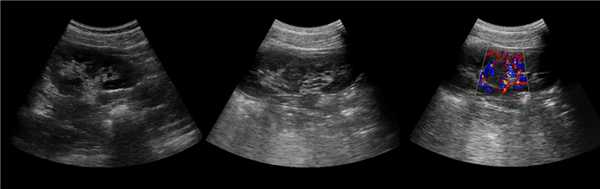

• Серошкальное УЗИ:

о Гомогенное округлое образование, изоэхогенное корковому веществу почки

о Расположена между почечными пирамидами

о Нормальные контуры почки

о Ограничена гиперэхогенной линией соединительной паренхимы и гиперэхогенным треугольным дефектом соединительной паренхимы

о Вдается в почечную пазуху с латеральной стороны

о Гиперэхогенность может быть обусловлена анизотропией

• Цветовая допплерография:

о Нормальная перфузия указывает на неизмененную почечную ткань

о Отсутствует деформация сосудов с нормальными дугообразными артериями, окружающими пирамиды

о Отсутствуют аномальные сосуды

(Левый) На рисунке показана бертиниева колонна, которая является не истинным новообразованием, а разрастанием коркового вещества почки между пирамидами.

(Правый) На продольном ультразвуковом срезе правой почки визуализируется гипертрофированная колонна Бертена, вдающаяся в клетчатку почечной пазухи в среднем отделе почки. Обратите внимание на ее изоэхогенность корковому веществу и гладкие наружные контуры.